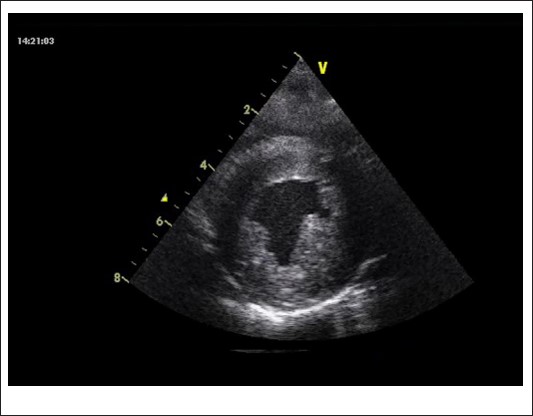

By age 4, progression to dilated cardiomyopathy (DCM) with further worsening of diastolic function was observed (LVEDV 84 ml/m2, LVESV 52 ml/m2, LVEF 38%) (Figure 2). The patient also exhibited psychomotor delay and moderate neurologic dysfunction - hallmark features of MELAS syndrome in children.

Figure 2: Hypertrophic left ventricle with DCM.